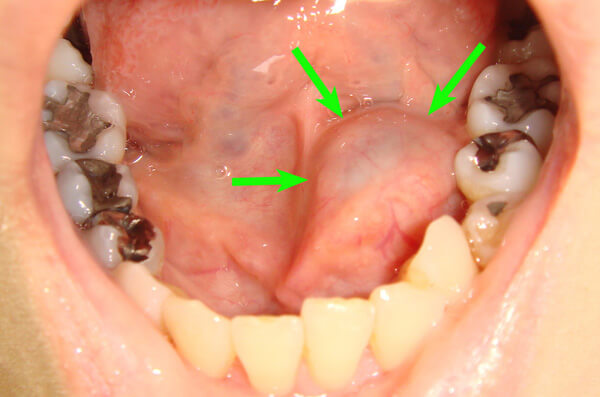

②軟組織に発生する嚢胞